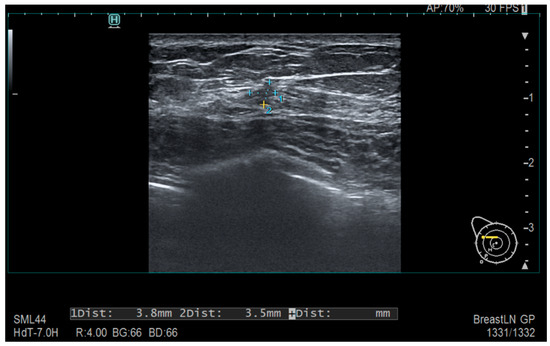

Tumors were classified using the WHO histologic criteria (such as invasive ductal carcinoma, invasive lobular carcinoma, ductal carcinoma in situ, and mixed histology). Age categories were used for analysis. Advanced imaging methods such as breast ultrasound (Figure 2), MRI (Figure 3), mammography (Figure 4), or CT were performed in only a subset of patients, highlighting significant shortcomings in early detection and screening practices within the healthcare system.

Figure 2. Ultrasonography—Diffusely contoured, hypoechoic area located in the external quadrant, measuring 3.8 mm × 3.5 mm.